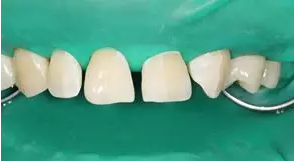

8.分層堆塑:硅橡膠背板就位于口內,使用瓷納美E2 色樹脂進行腭側堆塑,形成厚約為 0.5mm 腭側釉質壁,光照20s,移走硅橡膠背板,腭側繼續(xù)光照 20s。接著使用 D2 色樹脂進行充填,注意充填的厚度約為0.5mm,長度短于切端1~2mm,且頸部的厚度應逐步遞減。然后使用 E2色樹脂恢復唇面及切端,厚度約為1~1.5mm。堆塑時應兩顆牙同時進行,以便及時調整牙齒的寬度,堆塑完成后應檢查兩牙寬度是否一致,是否協(xié)調對稱,有無懸突等。

E2樹脂堆塑腭側釉質壁

移除硅橡膠導板后

D1 色,E2色分層堆塑完成